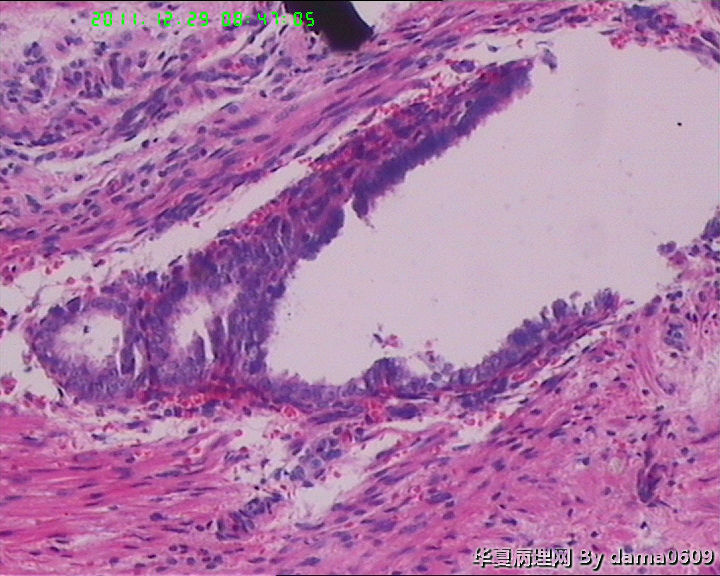

另一为小块囊壁样组织。镜下见卵巢间质内大量淋巴细胞、嗜酸性粒细胞浸润,间质出血。囊壁囊腔一侧见组织细胞、嗜中性粒细胞浸润,小血管增生(图1-9)。局灶见较多的平滑肌组织,内见有异位的子宫内膜组织(图10、11、12)。另于平滑肌组织间见到散在的小腺体(图13~30)。学生不解:1、老年人卵巢内可以出现平滑肌组织,如卵巢门处。此例如此多的平滑肌是正常的吗?   2、平滑肌间的小腺体若是异位的子宫内膜腺体但周围不见内膜间质成分。若非内膜异位腺体,学生又不知如何解释,尤其图19、20、21。请老师们指点迷津。感谢!!

• 感谢老师们一年来的支持,年终岁尾最后一贴,请老师们指教!!图11

图11